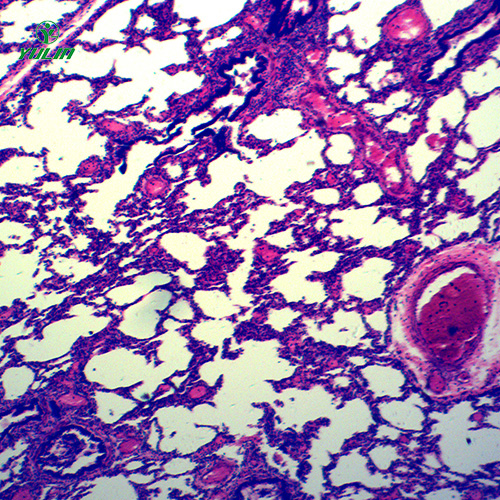

畜牧兽医宏观标本,循环系统浸制标本,循环系统浸制标本价格